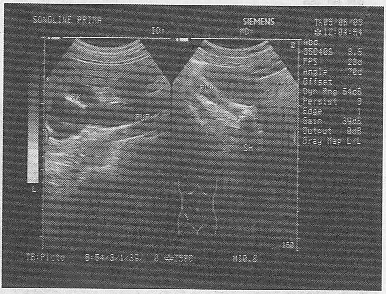

3._女,56歲,消瘦、腹部膨隆3個月余。婦科檢查:盆腔觸及包塊。超聲檢查如圖,最可能的診斷為

正確答案:B 解題思路:附區見無回聲暗區,其內見強回聲光帶分隔及散在浮動光點,囊壁不均勻增厚,可見乳狀光團突入囊內且有腹水。